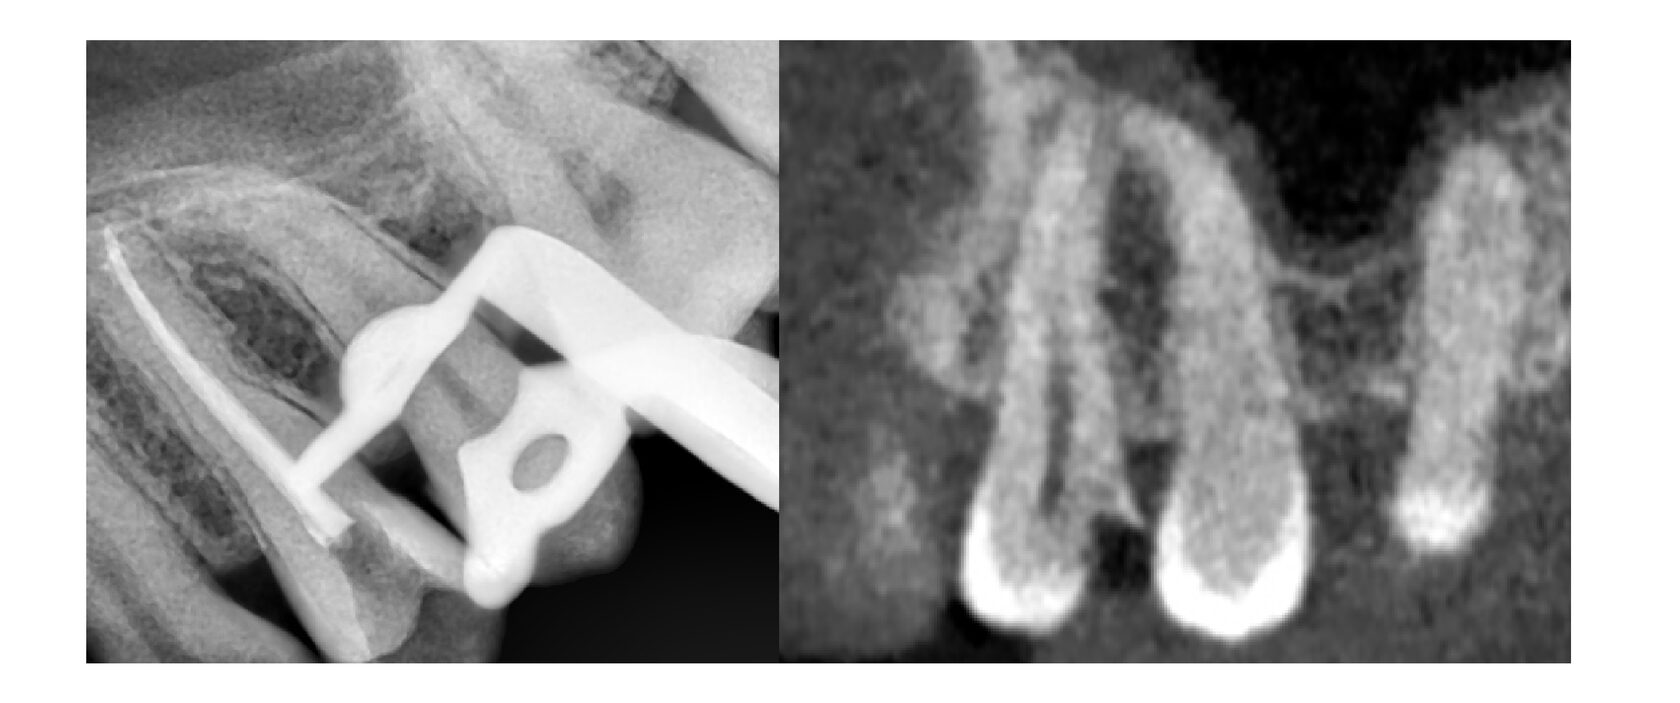

Пациент обратился к нам с профилактическим осмотром, на котором на зубе обнаружена небольшая кариозная полость, что также подтверждается снимком. Полость действительно небольшая, это означает, что кариес не добрался до нерва и требуется лишь постановка пломбы.